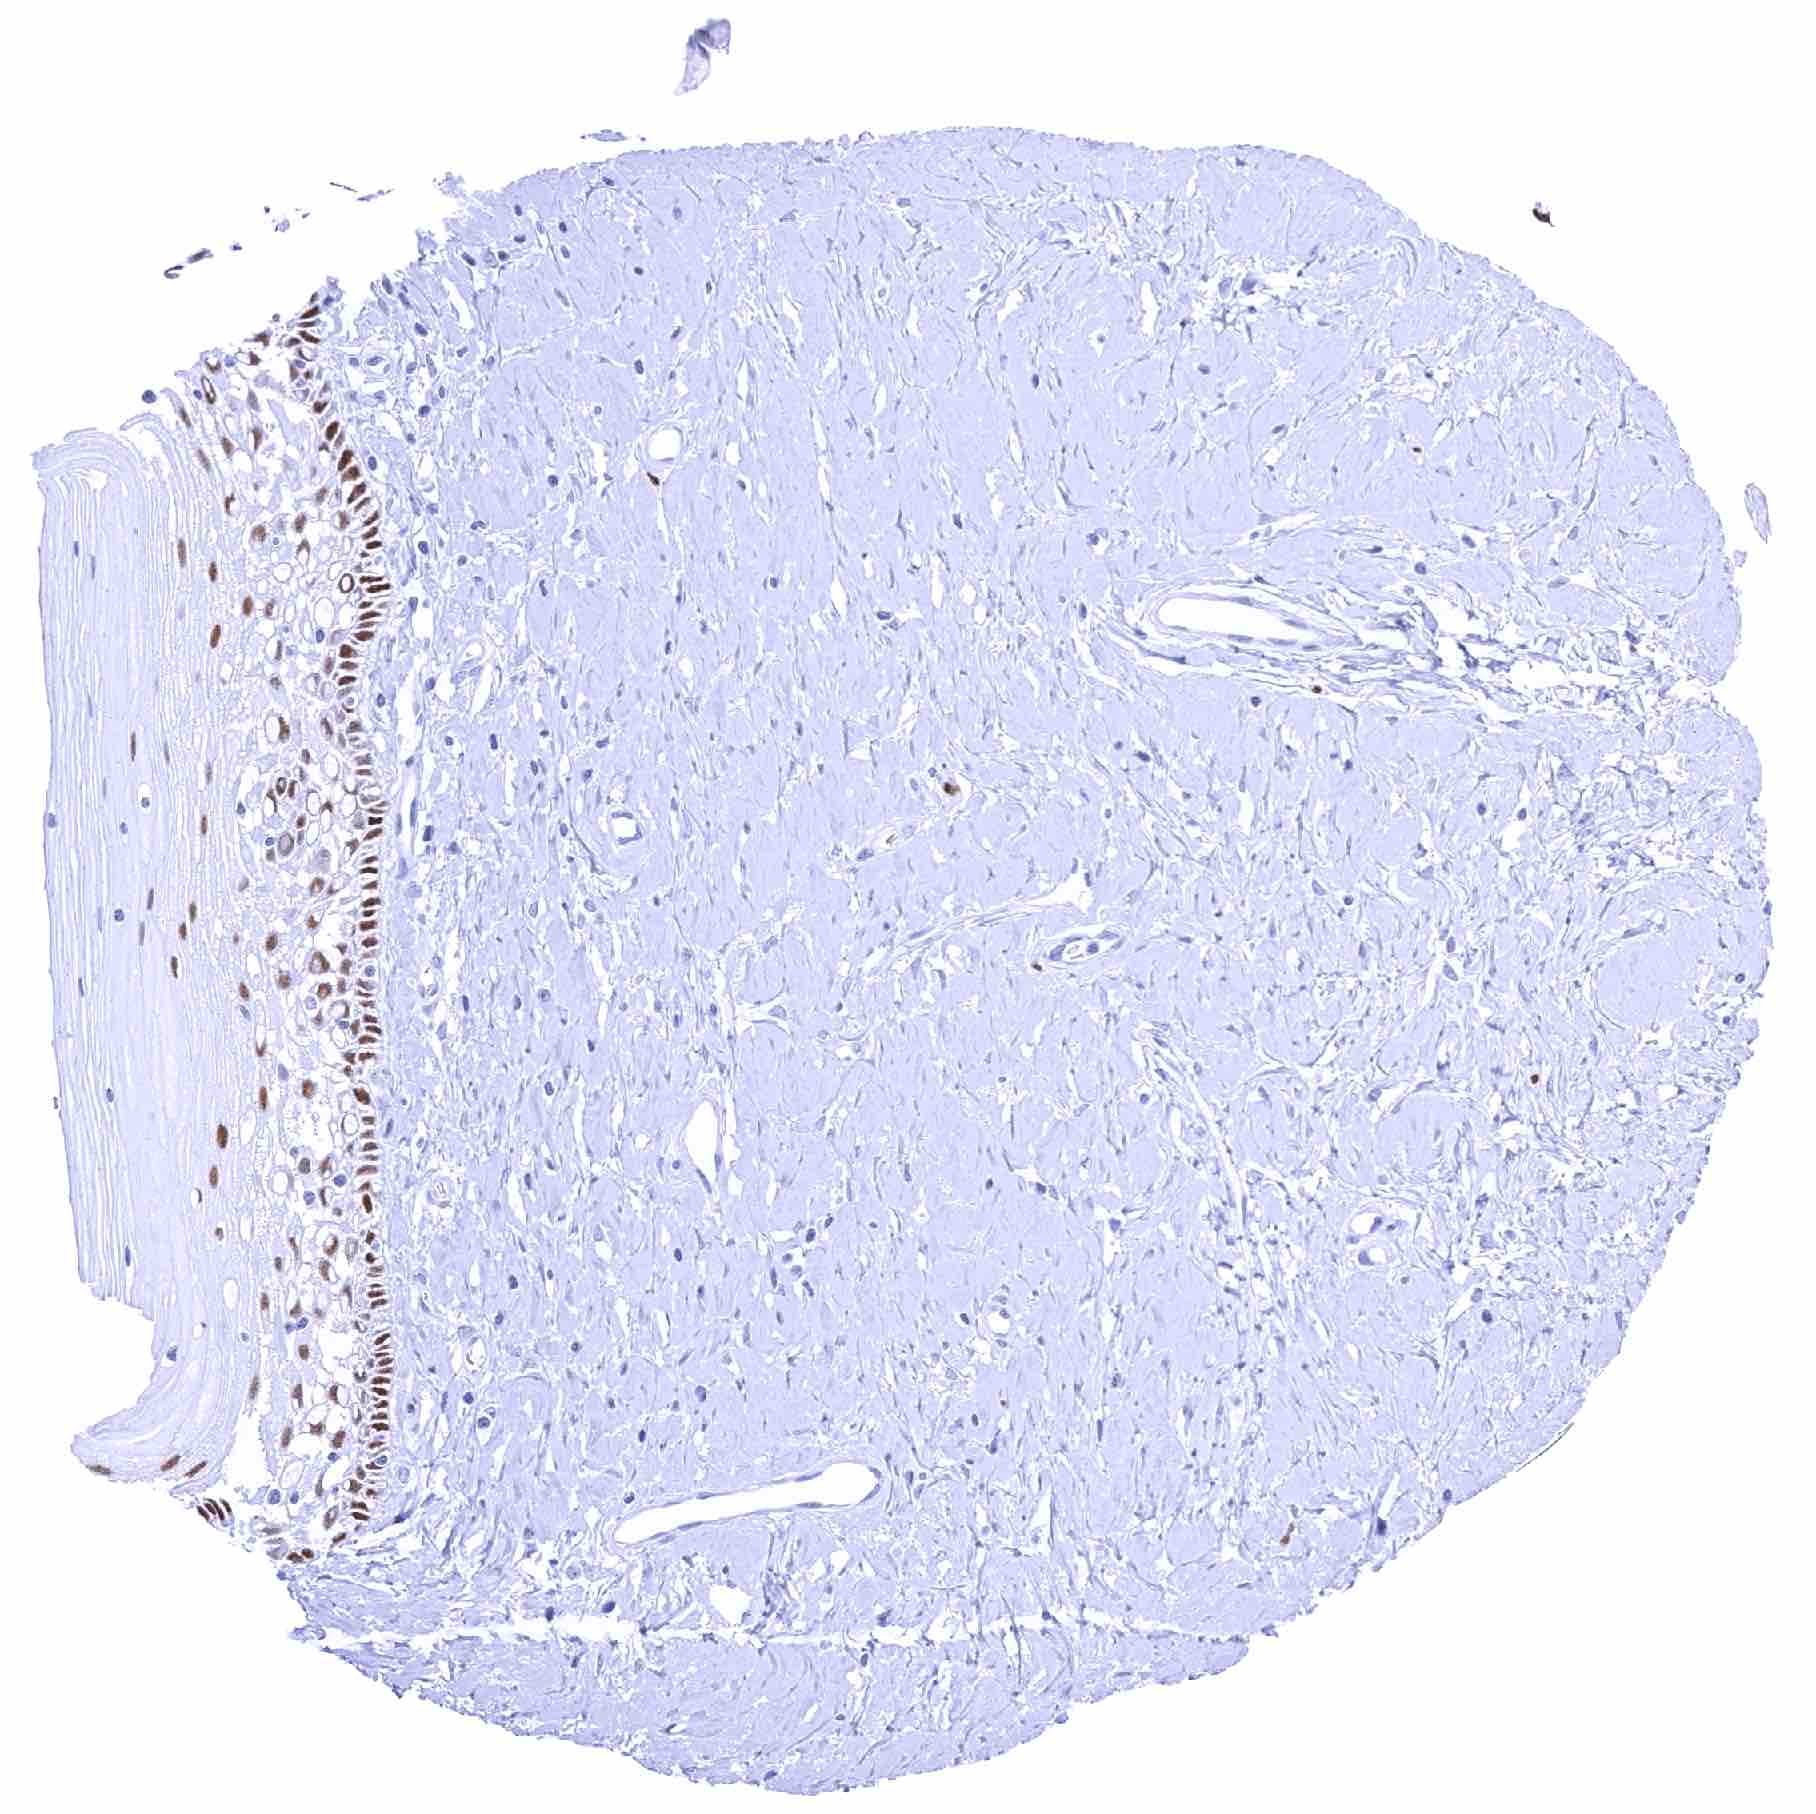

Uterus, endocervix – Weak to moderate SOX2 positivity of endocervical cells

Uterus, endocervix – Endocervical cells are SOX2 negative in this sample